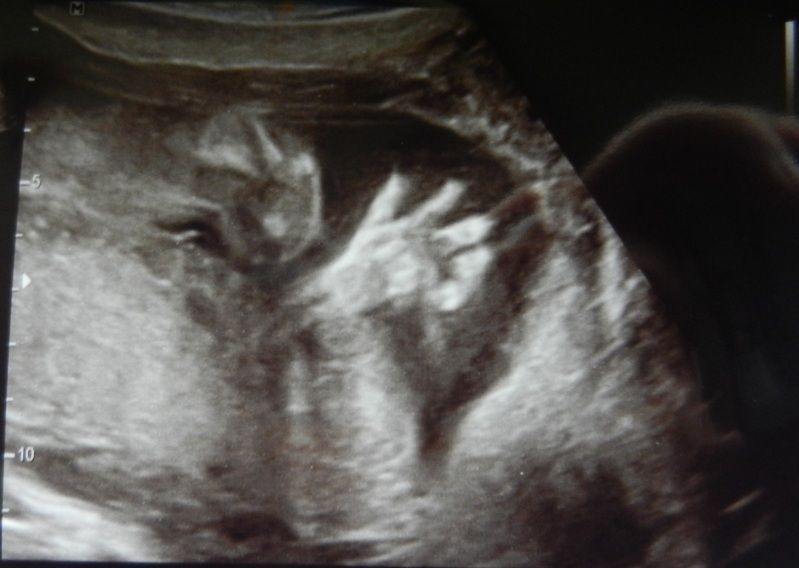

Maar goed, we zitten daar dus, die echo wordt op mn buik gezet en we zien dit.

Juist de baby die in koprol positie ligt :-/ Dus alle 3 met een vreemd gezicht naar dat scherm staren en alle 3 met het hoofd schuin. De echodame moest gniffelen en zei, ja soms tref je ze echt in de meest vreemde posities aan.

En toen de foto werd genomen zette de kleine zich net af wat ik dus echt voelde aan de buitenkant en zo werd voor mij bevestigd dat het de voetjes zijn die ik elke x voel schoppen(dacht nl misschien dat de kleine zich afzet en dat het kopje dan ergens tegenaan knalt). Wat een kracht in die minibeentjes zeg!

Verder was alles goed en de kleine is op week 20.0 21 cm en 311 gram en daarmee volgens de echodame een gemiddelde baby... Waarop ml commentaar gaf toen wij naar de auto liepen. Die zij, ik wil geen gemiddelde baby ik wil een aparte.. Haha, ik zei dus dat het over de lengte en gewicht ging! Owww zei die, haha... Hij had dus zoals ik had verwacht een slimme baby of een gemiddelde baby enz in gedachte.

En nog een(imo spookachtig) handje: